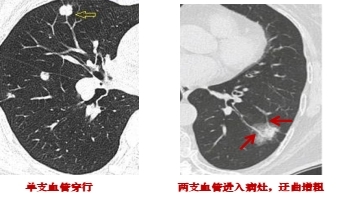

3.結節與血管的關系:如果肺結節內部有血管匯入,周邊有血管伴行,且血管扭曲、增粗、變細或被中斷,往往提示惡性。